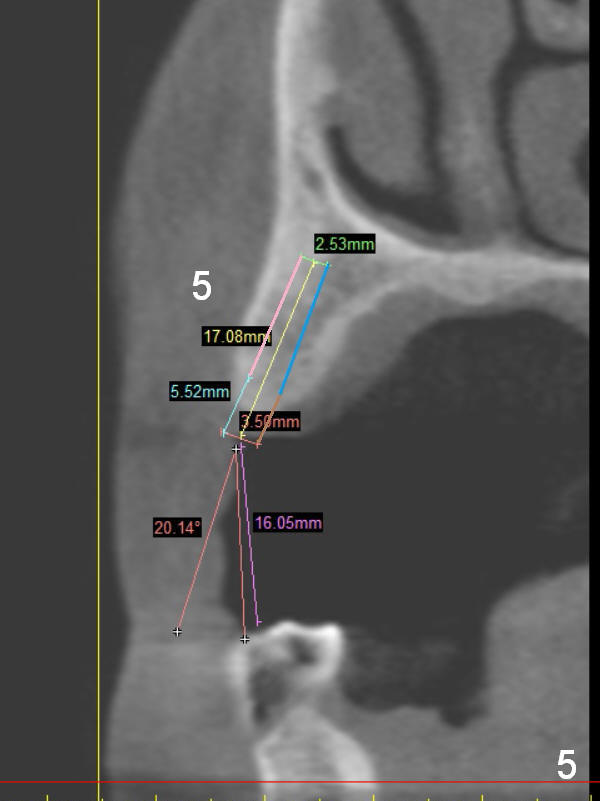

A 68-year-old lady has several missing teeth (Fig.1,2).  She has agreed to have an implant at the site of #3 (Fig.3) to stabilize an upper removable partial denture (RPD).  The latter will be more stable if an extra implant is placed at #6 (Fig.1,2,6).  There is enough bone to place implants at #4,5 (Fig.4,5).  Bone density at these sites is low.  Osteotomy should be underprep with bone condensation.  Edentulous space is high so long abutments are required (9 mm instead of 3 or 5 mm (regularly used)).  Angled abutments should be prepared.